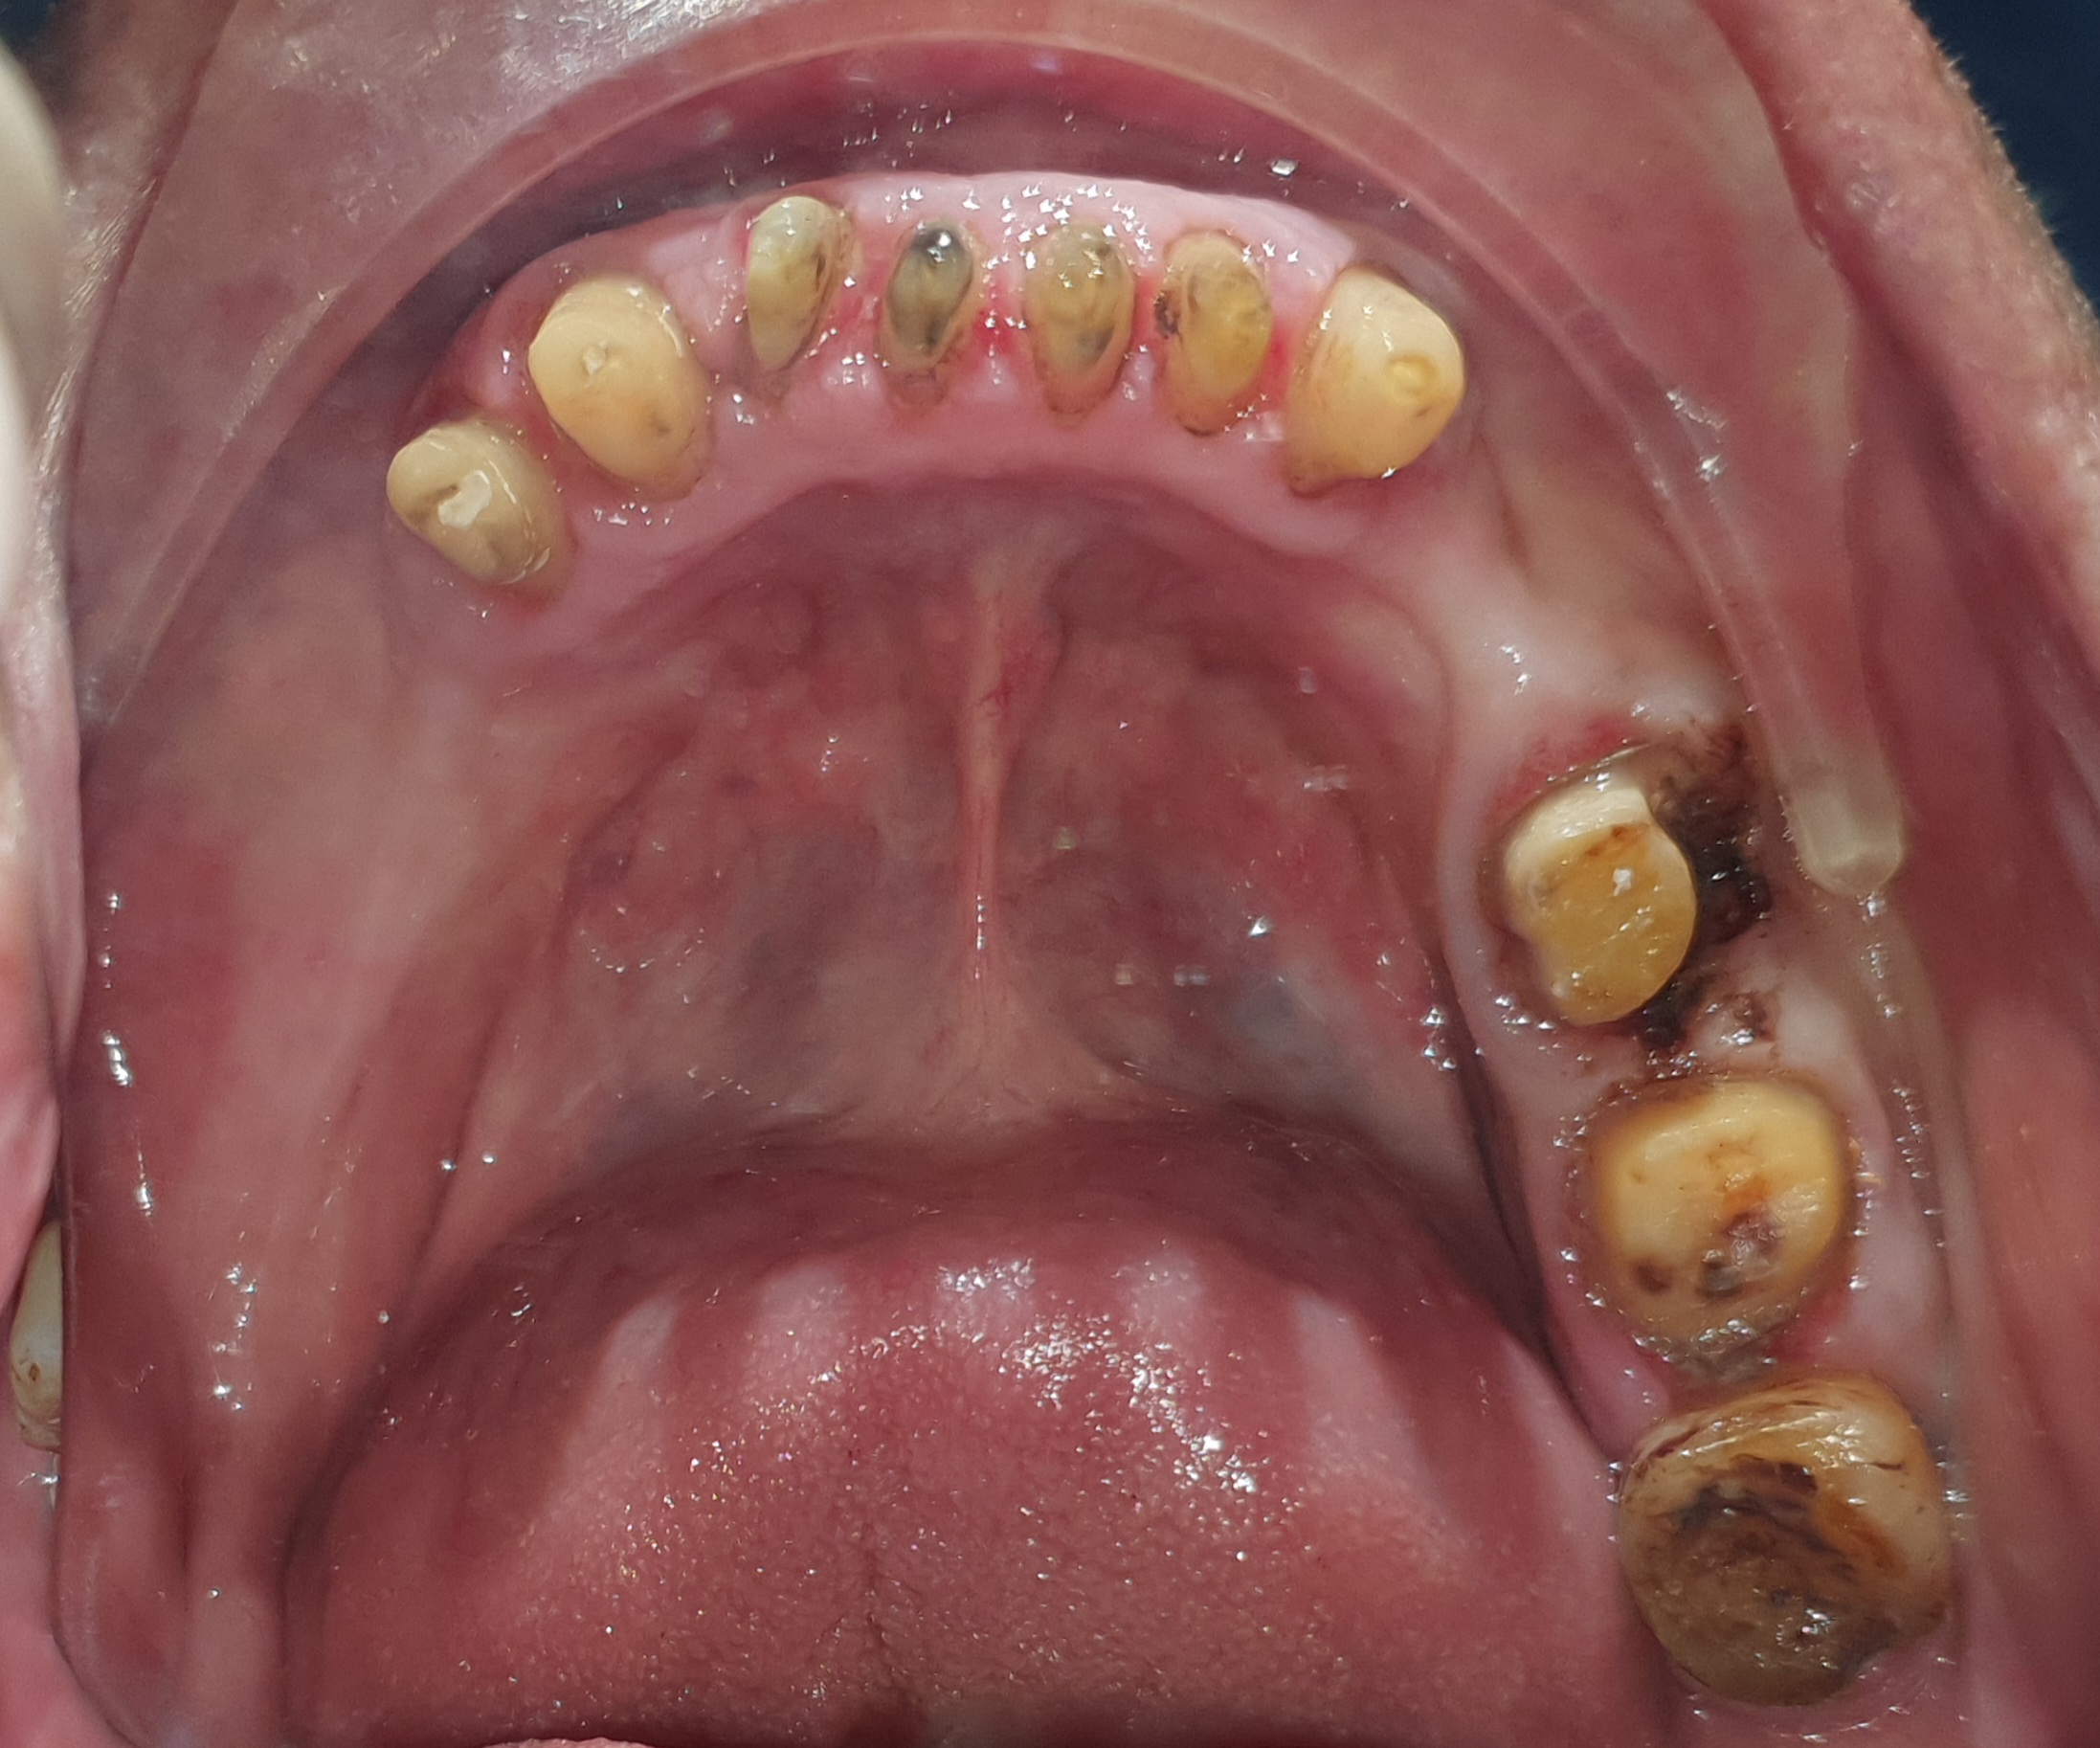

?Qua thăm khám thấy:

– Bị mất kích thước dọc, cắn sâu. Khớp cắn rất nhạy cảm với thay đổi, dù là rất nhỏ.

– Răng sứ hiện tại quá to, và thô, làm dính liền tất cả các răng sứ với nhau, rất khó vệ sinh, dẫn đến viêm nướu nặng.

– Răng thật còn lại thì mòn cổ nặng, có răng nhiễm trùng cần điều trị tủy

-….

Tình trạng răng ban đầu

Hình ảnh răng hàm trên và dưới